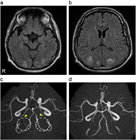

1. 高血圧性脳症は高血圧緊急症のひとつに含まれ、本来脳血管自動調節能(cerebral autoregulationを有する脳血管に閾値を超えた高血圧負荷がかかり、脳血管のvasospasmおよび血液脳関門BBBのbreak-through現象による血管原性浮腫を生じ、可逆的あるいは非可逆的な組織学的変化が起きる状態である。

1. 従来、このような病態はCTのみでは同定しにくいこともあったが、近年、MRI、MRA、脳灌流画像などにより、reversible cerebral vasoconstriction syndromeRCVSやPRESposterior reversible encephalopathy syndromeといったダイナミックな病態として捉えられるようになり、正しい診断が迅速な治療に結びつくようになってきた。